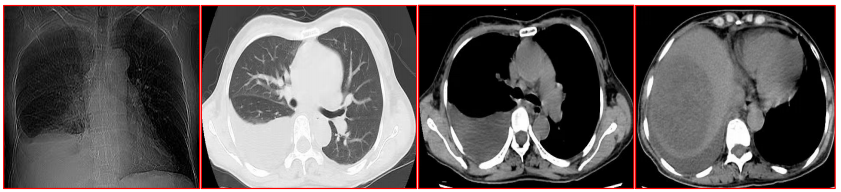

CT:右侧胸腔大量积液及膈肌右侧上抬继发右肺膨胀不全、左侧胸腔少量积液、心包少量积液、肝内巨大团块影(图1)。

图1. 肺部及腹部CT